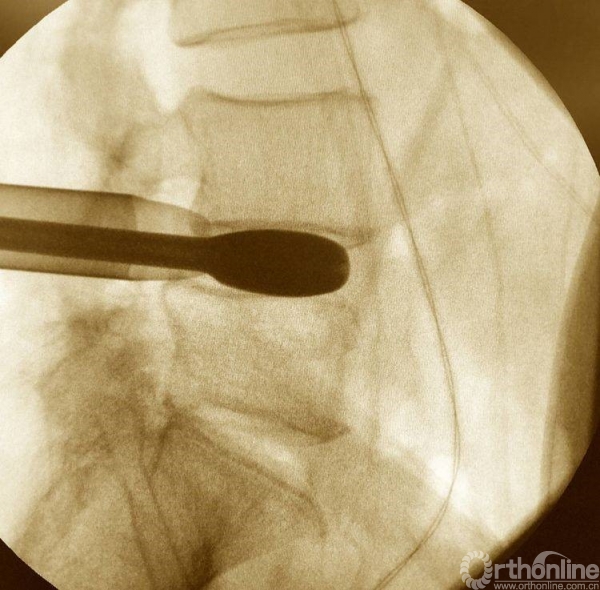

植入椎板钉、开路椎、扩展管、克氏针以及动力钻等应用

植入经皮椎弓根钉并加压

充分植骨(关节成型时的自体骨质、也可配合异体骨使用),然后植入融合器,镜下观察融合器和硬膜囊位置并透视再次确认

正侧位透视观察滑脱是否复位、融合器及植骨的位置

镜下观察有无碎骨块,融合器与硬膜囊位置关系